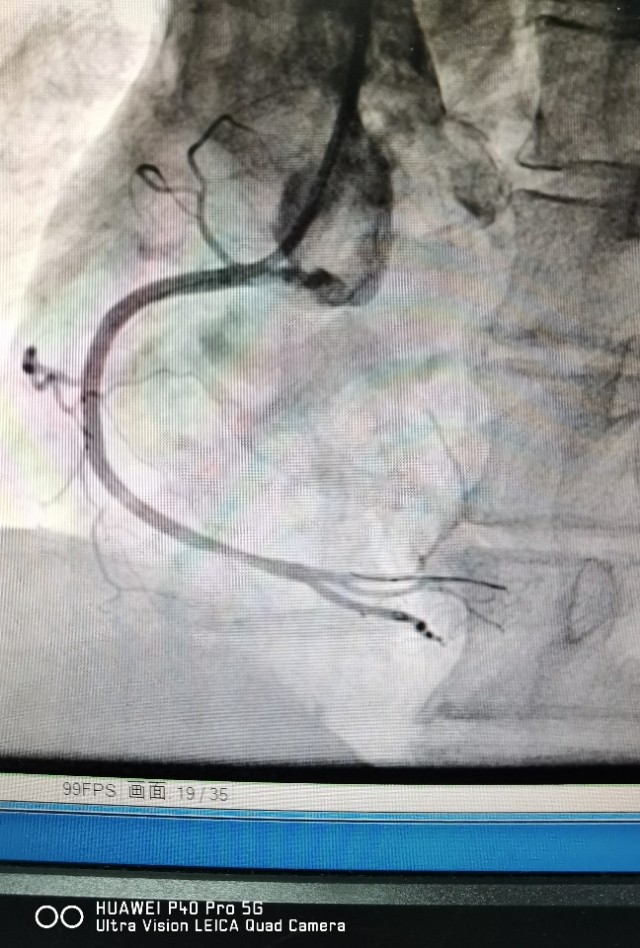

病例2 及时发现ACS斑块,避免心肌梗死发生

中年男性,反复不稳定心绞痛发作,冠脉CTA提示中重度病变,造影发现RCA弥漫病变,OCT发现冠脉内红色,白色血栓形成,随时可能发生心肌梗死!

植入支架后恢复良好,患者胸痛症状消失!